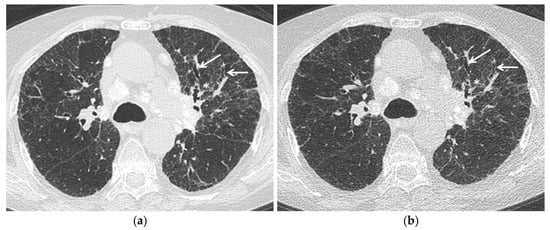

Since the potential advantages described above and the need to keep the radiation exposure as low as possible, studies are needed to validate these radiation-saving techniques in sarcoid patients, in particular in disease monitoring and, although uncommon, in children (Figure 1).

Figure 1.

Stage IV pulmonary sarcoidosis. Comparison between (a) standard chest HRCT acquisition (effective dose 3.3 mSv) and (b) Ultra-low dose acquisition (effective dose 0.8 mSv) with a 75% radiation dose reduction. Fibrotic changes—specifically irregular interstitial thickening (asterisk) and traction bronchiectasis (arrows)—are clearly evident at Ultra-low dose acquisition. Mediastinal calcified lymph nodes are also evident.